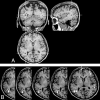

Fig 1.

3D T1-weighted images from 1 participant showing multiple dVRS. A, Cystiform dVRS are analyzed on axial, coronal, and sagittal planes. B, Multiple dVRS exhibit a linear shape and orientation along cortical medullary arteries (thin white arrows) in the white matter. Cystic dVRS (large white arrows) are detected on contiguous sections showing a cavity with a vascular shape extension.